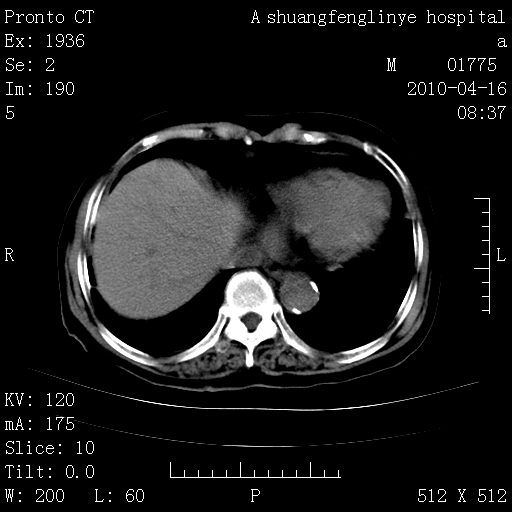

陈旧性结核,胃腔扩大,脾脏受压后移

典型 夹层动脉瘤。 内膜瓣钙化移位

1)左肺上叶结核(纤维、增殖病灶)。2)冠状动脉及主动脉钙化。肺动脉高压